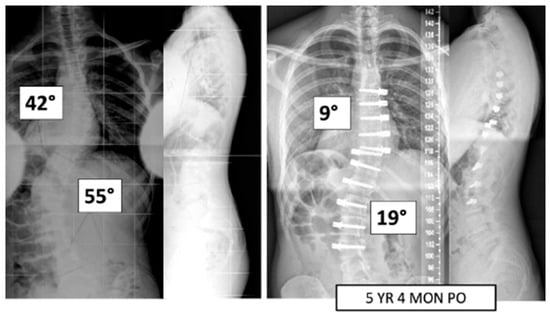

Figure 1.

This is a 15-year-old male treated with bilateral VBT instrumentation. At 5 years and 4 months post operation, he has returned to all activities.